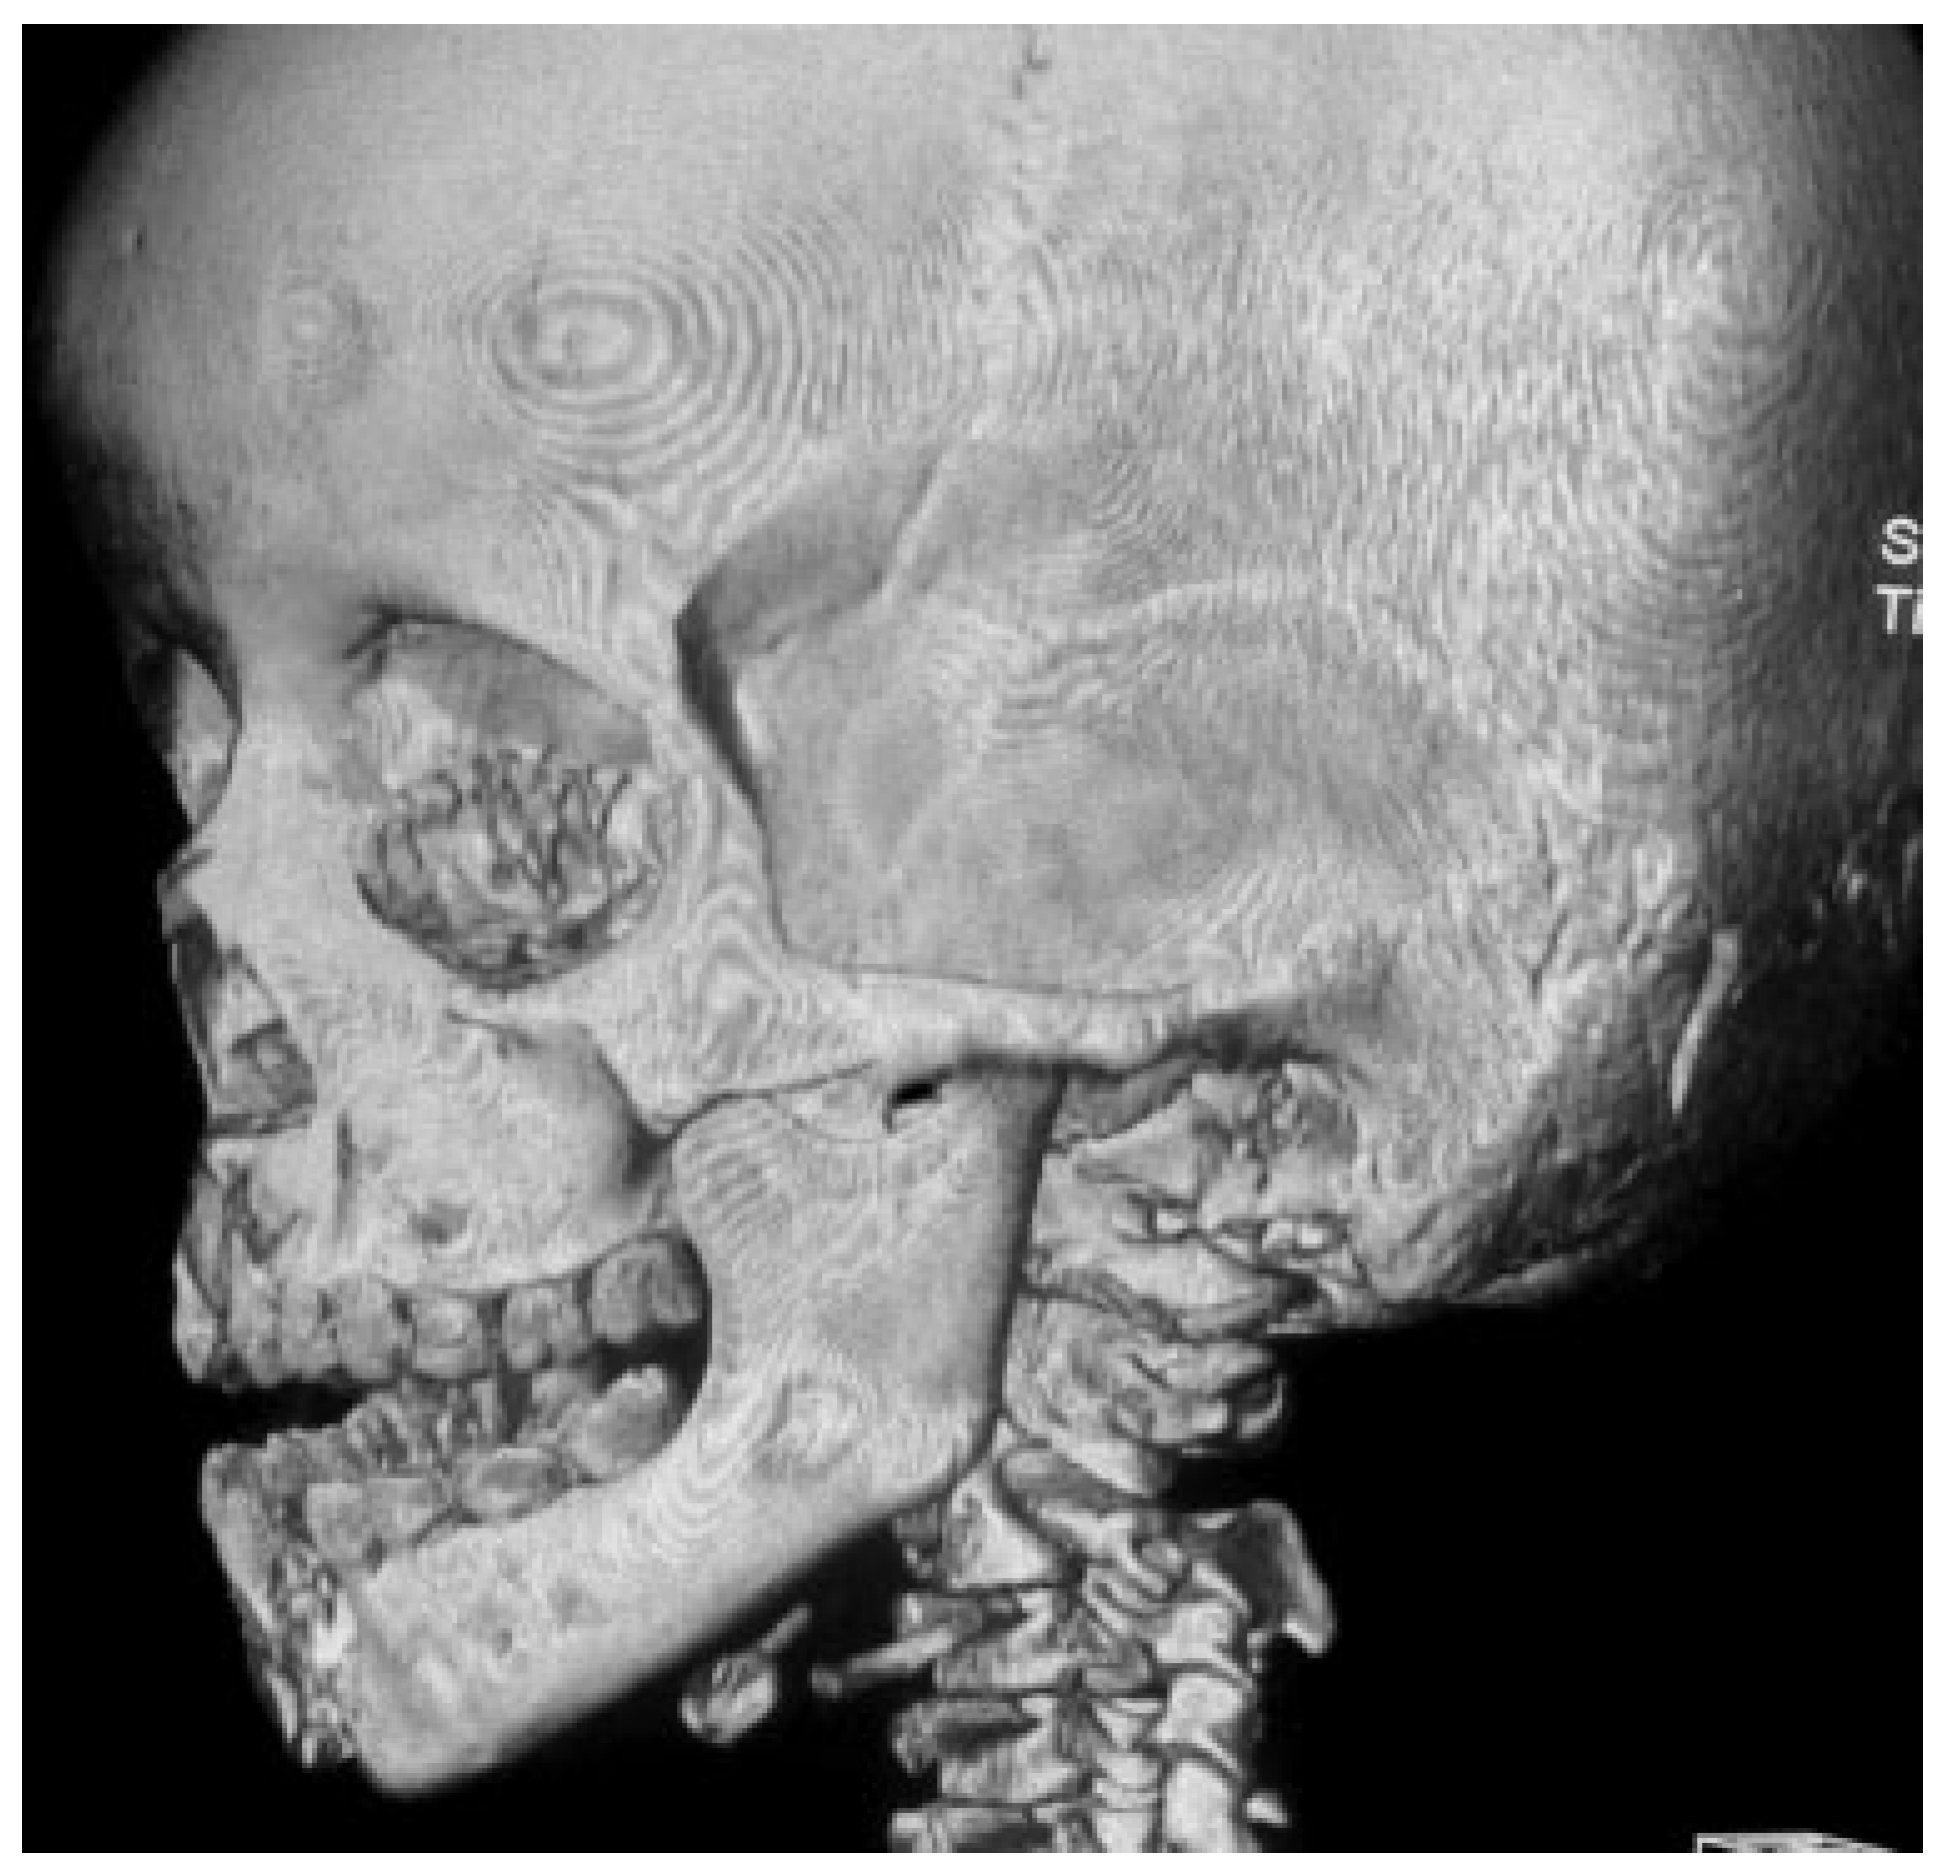

Unusual Superolateral Dislocation of Mandibular Condyle

Case Report